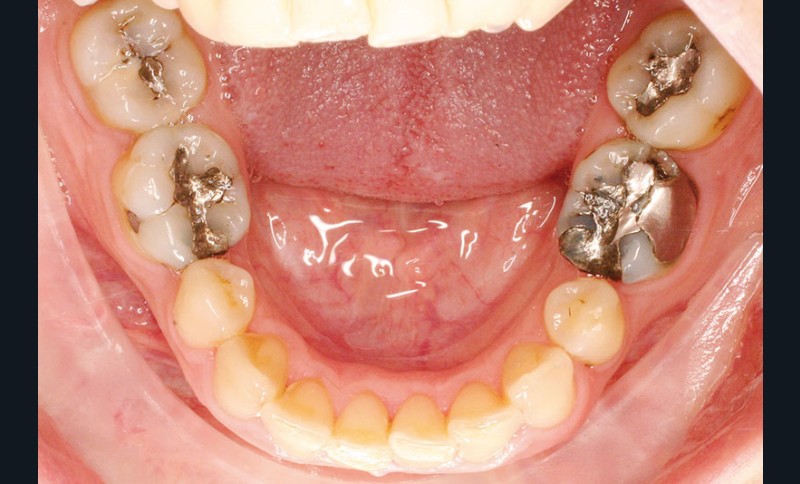

La patiente, âgée de 30 ans, présente des agénésies multiples : 12, 22, 14, 15, 24, 25, 35 et 45 (fig. 1 à 3).